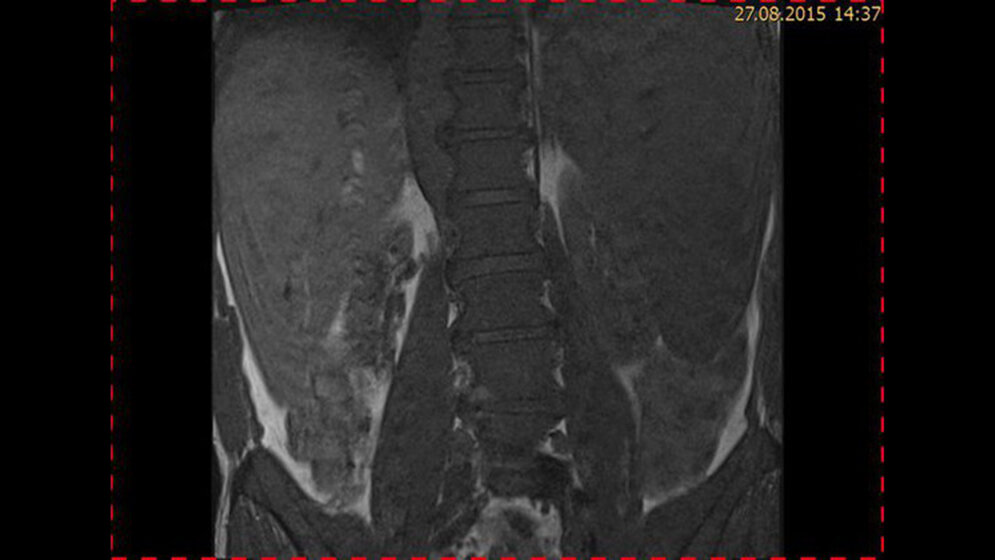

Tumoröse Veränderungen: Non-Hodgkin-Lymphom

Das Knochenmark ist das viertgrößte Organ des menschlichen Kör-pers und seine Hauptfunktion ist die Hämatopoese. Maligne lym-phatische Erkrankungen nehmen an Zahl zu und viele haben eine schlechte Prognose. Es gibt zahlreiche Risikofaktoren wie Bestrahlung, Chemotherapie, Chemikalien und andere. Es gibt Beweise, dass Blut-transfusionen mit einem erhöhten Erkrankungsrisiko und Mortalität in einem dosisabhängigen Verhältnis in Verbindung stehen. Das Lym-phommanagement erfordert ein exaktes Staging vor und während der Behandlung.